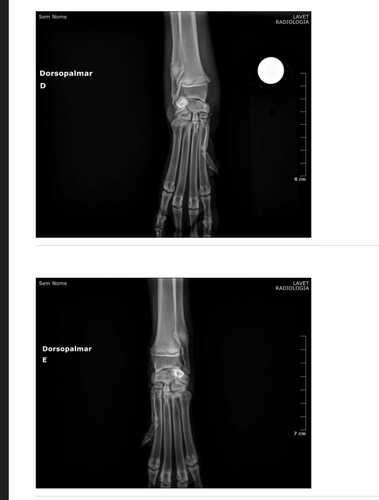

Ela tinha uma ferida aberta na pata anterior direita e não conseguia movimentar as patas traseiras. Os exames de imagens constataram duas fraturas, uma na pata da frente e outra na pelve. O ultrassom dos órgãos internos não constatou nenhuma alteração.

A fratura da pata dianteira precisou apenas de imobilização, mas para a da pelve, foi necessário realizar uma cirurgia. A cirurgia foi bem sucedida e a Lom está se recuperando nesse momento.